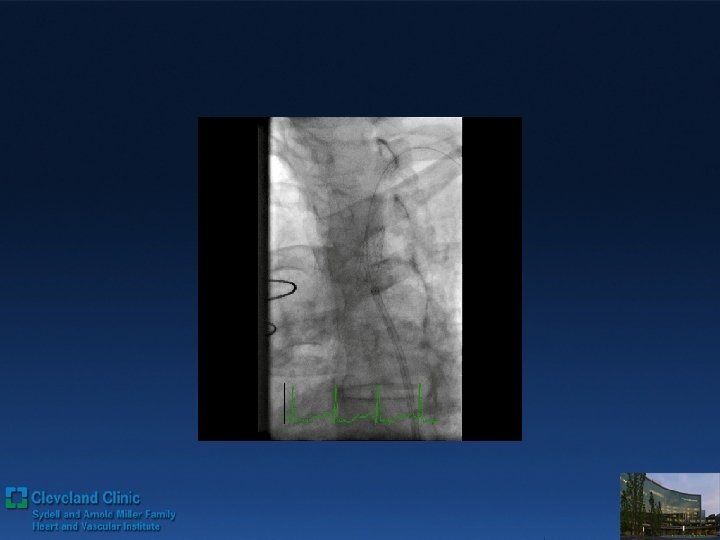

Direct Retrograde Crossing Via LAD Septal route Retro wire: Fielder FC® over the 2.

Direct Retrograde Crossing Via LAD Septal route Retro wire: Fielder FC® over the 2. 5 mm OTW Balloon

Direct Retrograde Crossing Retro grade wiring with wire trapping inside of ante grade Guide

Direct Retrograde Crossing Retro grade wiring with wire trapping inside of ante grade Guide 3 DES deployed